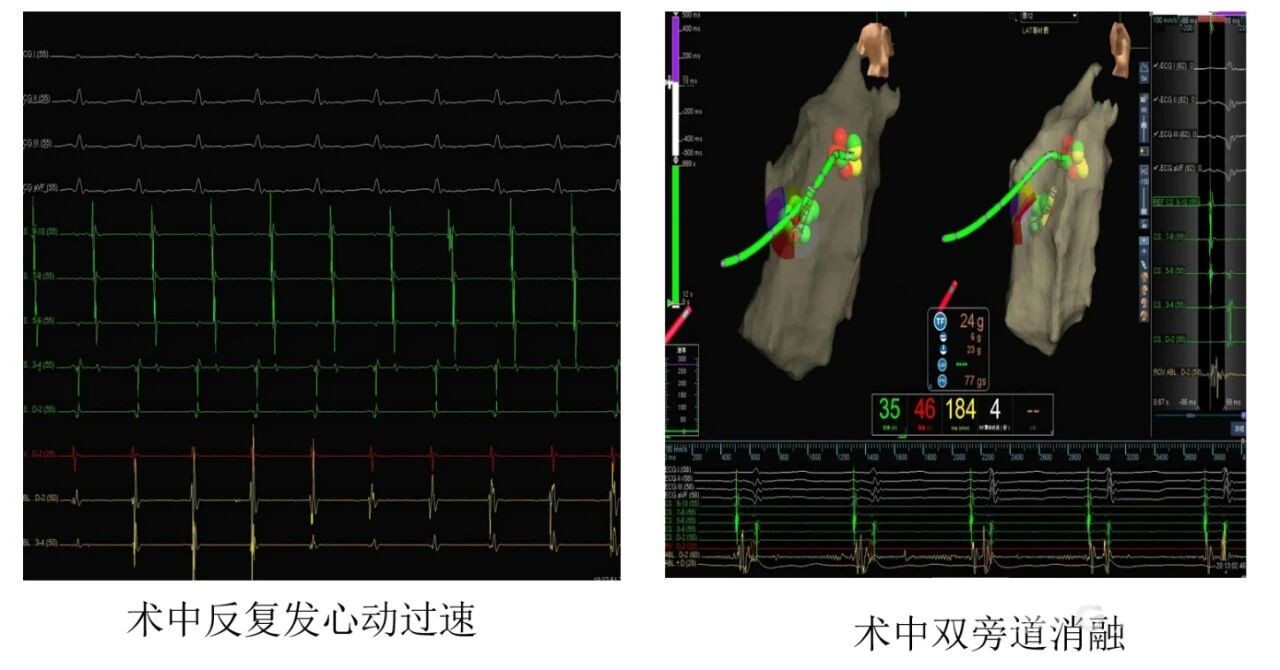

手术当日,在全身麻醉的状态下,贵医附院心外科团队首先为患者建立体外循环,并切开右心房,为内科电生理团队创造了清晰、稳定的操作窗口。随后,心内科电生理团队在心脏直视下,沿三尖瓣环进行精细的激动标测。

凭借三维标测系统与直视条件的双重优势,贵医附院心内科团队精准定位了包括位于憩室处高危旁道在内的右侧双旁道,并顺利实施了射频消融,成功阻断两条异常的“电路”。

手术当日,在全身麻醉下,心外科团队首先为患者建立体外循环,切开右心房,为内科操作创造了开阔、稳定的直视手术视野。随后,心内科电生理团队“上台”,在心脏静止和直视条件下,利用三维标测系统进行精细标测,精准锁定了位于憩室处的“高危”旁道及另一条右侧旁道,并成功实施了射频消融,彻底阻断了异常“电路”。